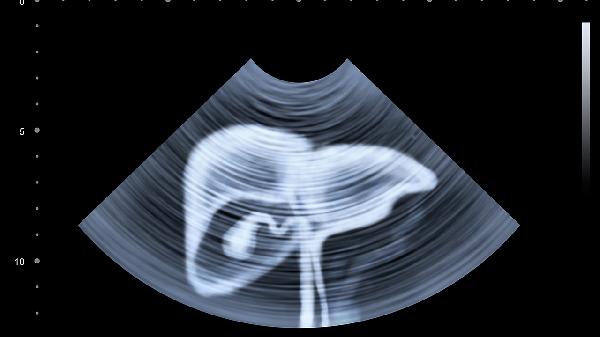

胆囊B超检查需要胆囊处于充盈状态以便清晰显影,空腹可减少胃肠气体干扰。检查前8-12小时需完全禁食,包括牛奶、咖啡等含脂质或刺激性饮品。若口渴难忍,可在检查前2小时饮用少量清水润喉,但需向医生说明饮水量。检查当天应避免嚼口香糖、吸烟等可能刺激胆汁分泌的行为。穿着宽松衣物便于暴露检查部位,金属饰品需提前取下。